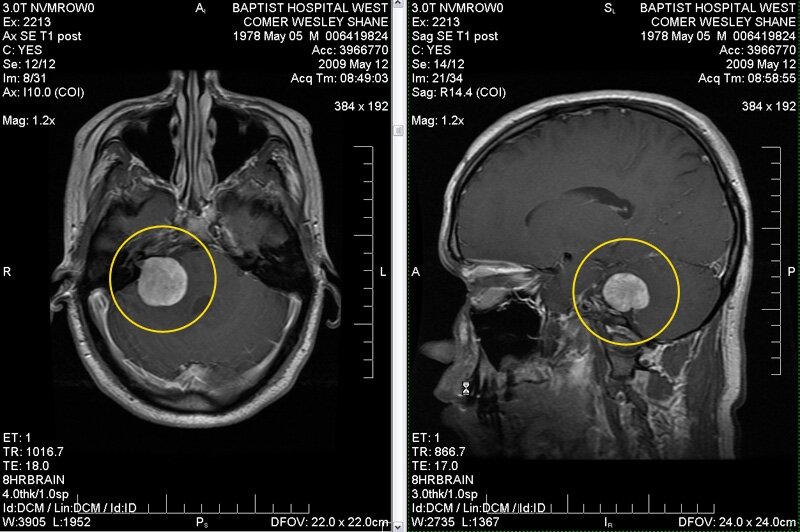

Опухоль мозга